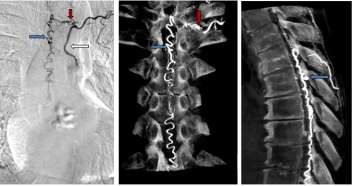

• CT scan of Type I Spinal Dural Arteriovenous Fistula

Figure 1. Type I Spinal Dural Arteriovenous Fistula - Spinal angiogram (left image) of a left sided spinal segmental artery (white arrow) with an abnormal connection (red arrow) to a spinal cord vein that has become abnormally enlarged (blue arrow)

• These malformations represent 70% of spinal vascular malformations and are the result of an abnormal connection forming between an artery and a vein in the spinal canal dural covering (Figure 1). This connection allows high pressure arterial blood to escape into the low-pressure network of spinal cord veins. Over time, the spinal cord is damaged by the elevated pressure in the veins. Spinal dural arteriovenous fistulas (AVFs) are thought to form spontaneously during adulthood and are not congenital or hereditary. These lesions rarely rupture or bleed, but they do cause significant spinal cord dysfunction that can result in leg weakness, lower body numbness, imbalance, and urinary problems. These malformations are good candidates for surgical treatment and endovascular treatment, which are typically curative.